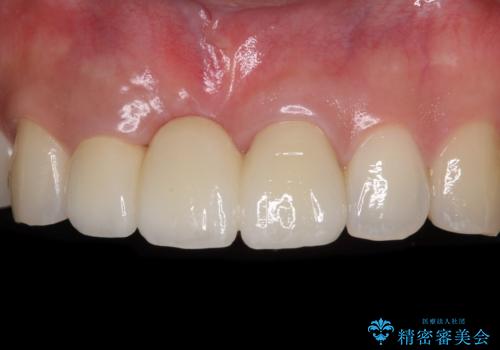

歯肉移植により歯肉ラインや歯の形態を整えることができ、ブリッジによる補綴としたことで舞えば全体の色調を整えることができました。